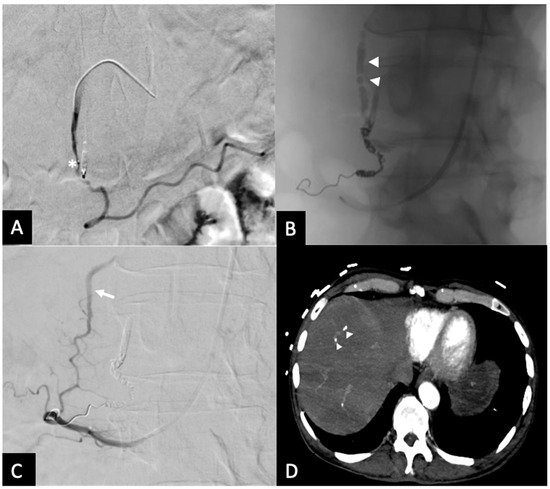

Figure 3. Seventy-three y.o. male with a large bleeding duodenal ulcer. Representative example of open-sandwich technique—(A) Post-embolization spot radiograph showing a 3 × 12 mm EmboldTM fibered coil (arrow) in the proximal right gastroepiploic artery (RGEA) and a continuous column of Ta-OCE (arrowhead) extending from the coil pack in the proximal RGEA to the proximal gastroduodenal artery (GDA) (B) Digital subtraction angiography (DSA) with contrast injection from the common hepatic artery (CHA) shows no flow in the GDA, RGEA, or any proximal branches, such as the supraduodenal artery (SDA). Image obtained from patient’s chart. Source: NK.